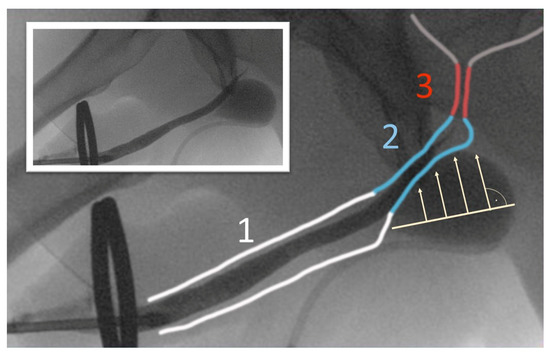

- Delivery of the tip of the tunneller paraurethrally below the hiatus urogenitalis, underneath the membranous urethra. As previously described by Rheder et al. for the fixed male Sling Advance, the entrance of the introducer needle tip into the perineal wound should be in the uppermost corner between the inferior pubic ramus and urethral bulb (Figure 5);

- The tunneled mesh arms were fixed using high tension to achieve an increased contact pressure of the cushion (in Cases 3 and 4) (Figure 6).